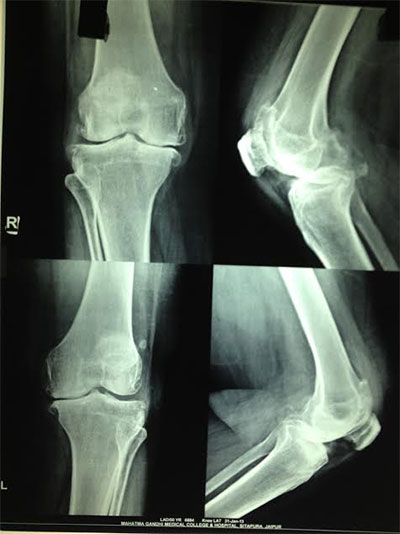

The knee is the most used and therefore stressed joint in the body. The common causes of pain in the knee are injury, arthritis and infection.

If your knee pain is so severe that it causes difficulty in walking and performing daily activities, knee replacement might be called for. However it is mandatory that these symptoms be taken to a doctor for an accurate diagnosis. Doctors try and delay the procedure for as long as possible by using non-invasive treatment. However if the disease is in an advanced stage, knee replacement is a means to achieve relief from pain as well as return to daily activities.